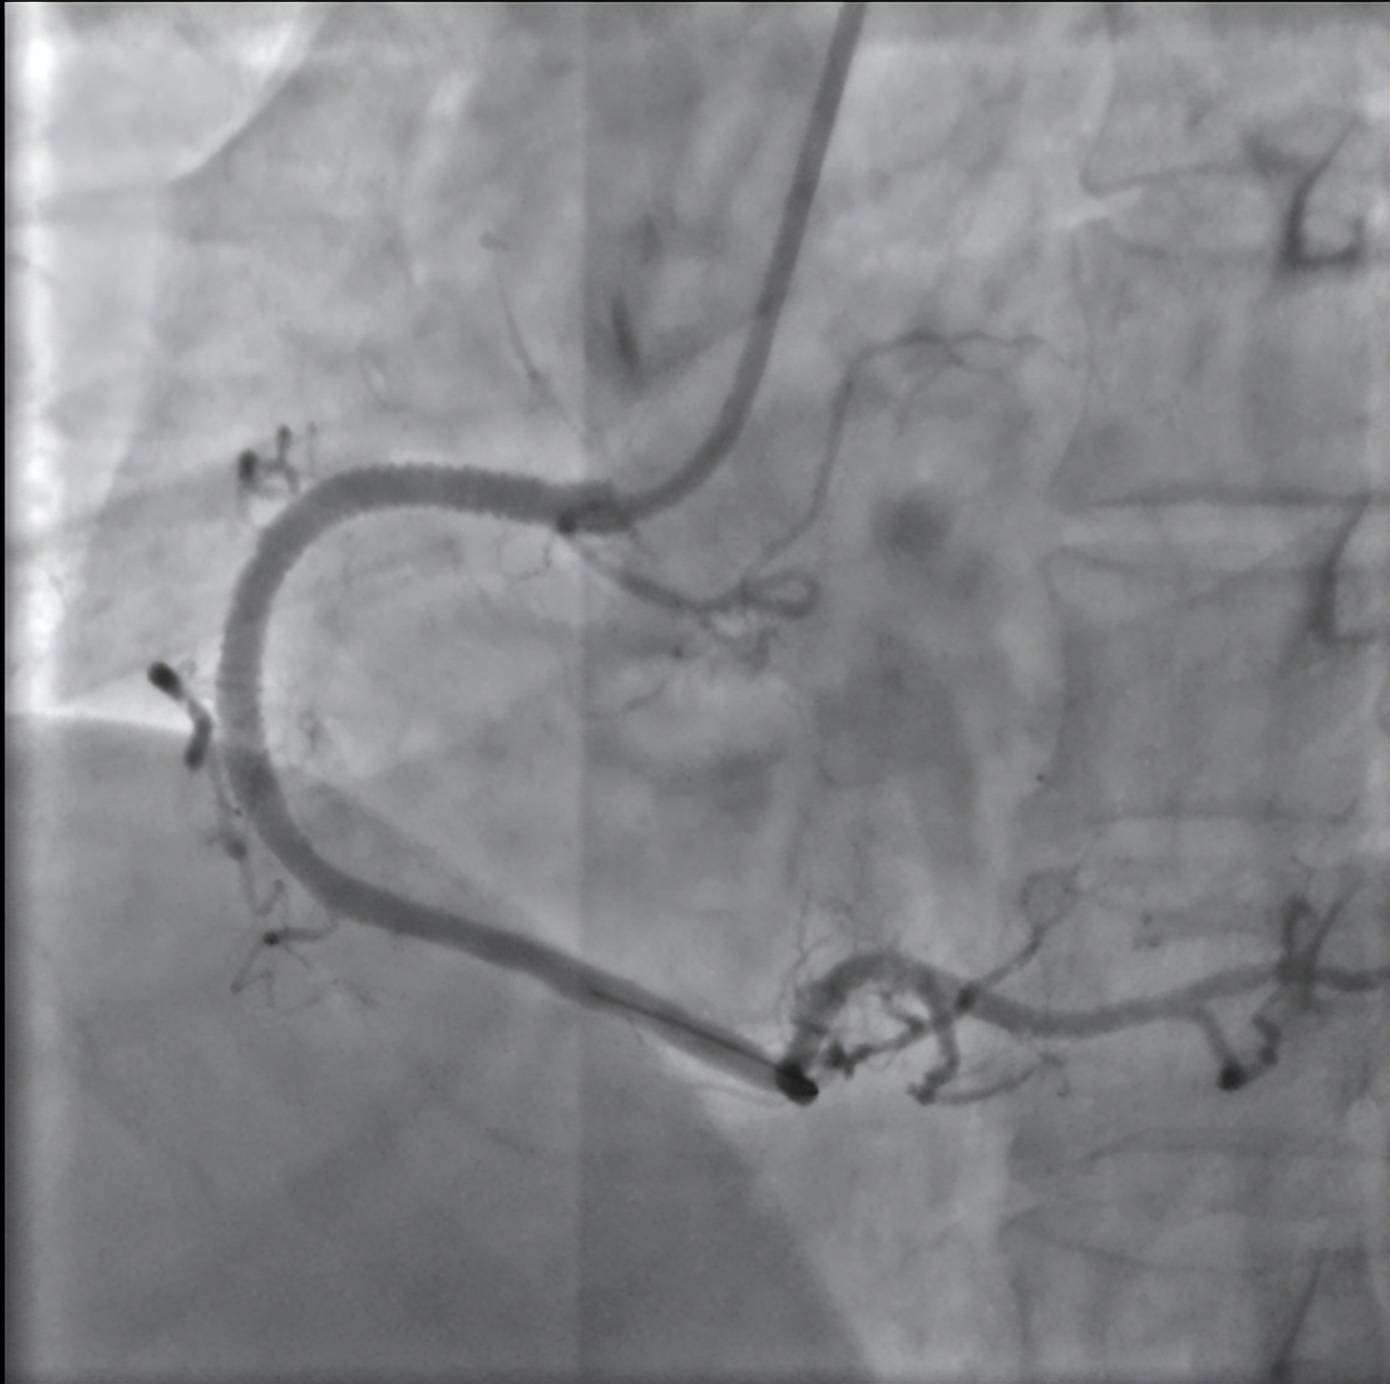

植入支架之后的右冠状动脉

一场与时间的赛跑随即展开,泰康同济胸痛中心立即启动急性心肌梗死救治绿色通道,急诊冠状动脉造影显示郑先生右冠状动脉完全闭塞。从进入医院大门到手术器械成功开通堵塞血管仅用时51分钟,远低于国际公认的90分钟黄金标准。术后郑先生胸痛症状迅速缓解,生命体征逐渐平稳,目前已转入普通病房观察。